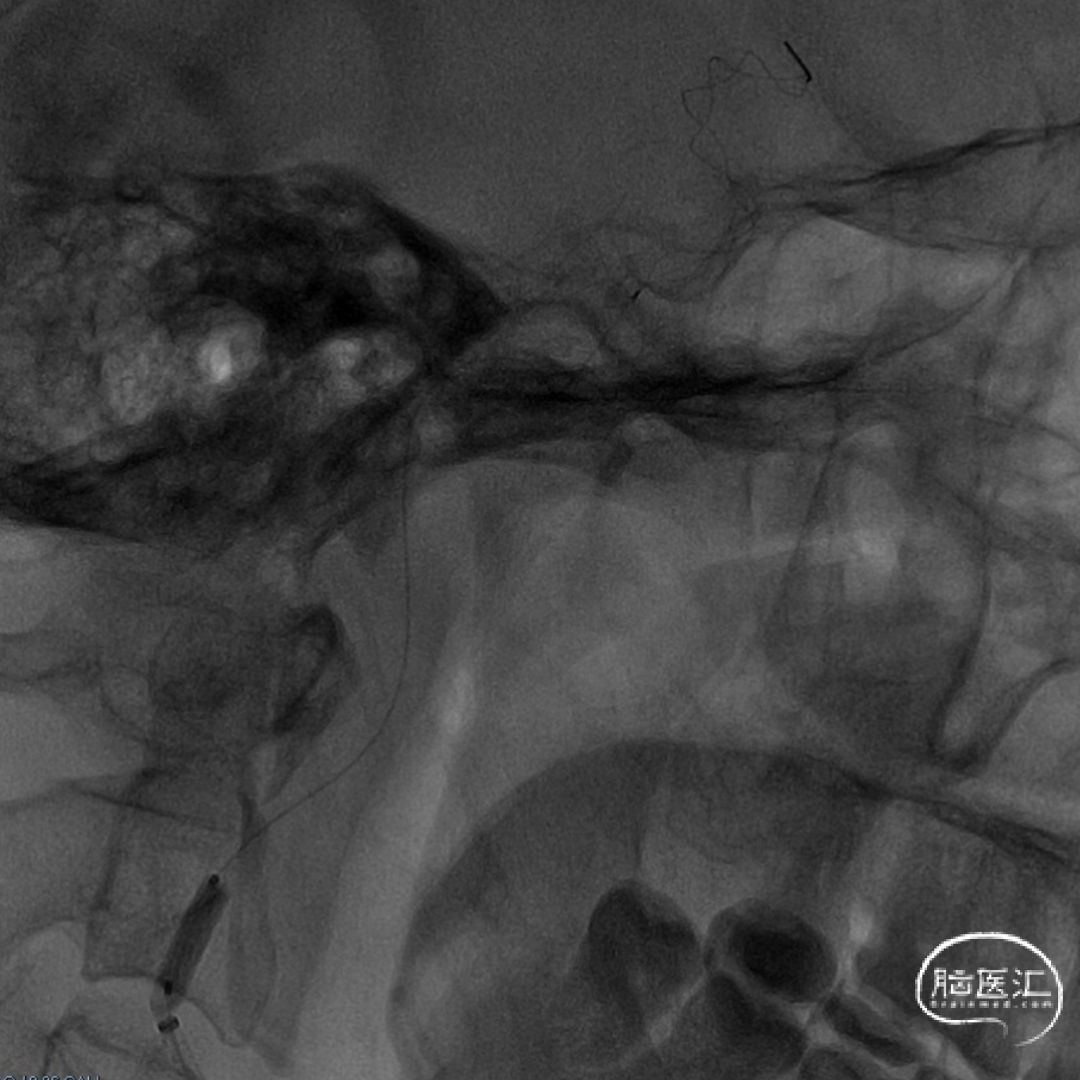

· 遂再次送入 3.0×12mm SacSpeed®球囊扩张导管于C1段远端以8atm扩张,并逐渐释放,同时跟进中间导管至C5段,继续前送中间导管在负压抽吸下将保护伞回收至中间导管内,并持续负压下将保护伞撤出,保护伞及抽吸注射器内无明显血栓碎片,撤出中间导管、8F Guiding。

术后即刻影像。

支架植入后造影提示残余狭窄约10%。术中患者生命体征稳定,术后患者恢复良好出院,继续抗血小板聚集及他汀类药物治疗。